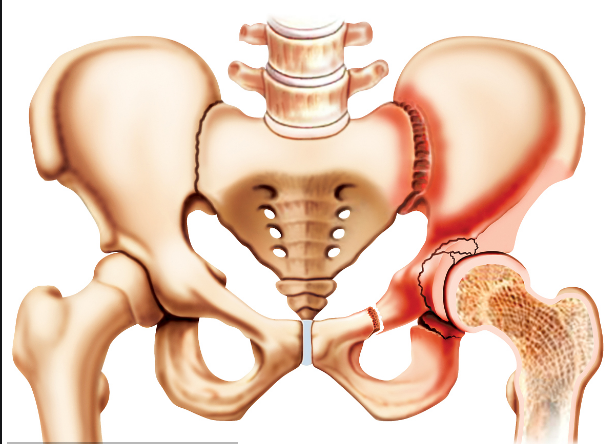

人體的髖關(guān)節(jié)是一個(gè)杵臼關(guān)節(jié),就像我們生活中常見的器物杵臼。“杵”就是我們的股骨頭,而“臼”就是指我們的“髖臼”。我們知道,正常情況下,“杵”是嵌在“臼”里面的,有豐富的肌肉保護(hù)著,但是,當(dāng)“臼”的結(jié)構(gòu)不正常時(shí),“杵”在肌肉的作用下就會從“臼”里慢慢跑出來,導(dǎo)致無法正常發(fā)揮作用。近日,瀘州市中醫(yī)院骨三科開展的市屬醫(yī)院首例髖臼周圍截骨術(shù)PAO, 就成功為一名成年患者解決了“杵”與“臼”結(jié)構(gòu)不正常的問題。

隨后,肖女士來到瀘州市中醫(yī)院治療。經(jīng)醫(yī)生檢查,引發(fā)她疼痛的原因竟是因?yàn)樗淖笸润y臼先天性發(fā)育不良。值得注意的是,肖女士并沒有遺傳史,也沒有外傷史,在不疼時(shí),她的雙腿看起來和正常人并無異樣。

“髖臼發(fā)育不良其根源在嬰幼兒時(shí)期已經(jīng)存在,由于未及時(shí)發(fā)現(xiàn)或治療不徹底而殘留下來 。”瀘州市中醫(yī)院骨三科主任、主任中醫(yī)師李彬介紹,肖女士的髖臼因發(fā)育不良,淺且覆蓋少,因此,造成她的髖臼對位不好。在走路時(shí),因?yàn)榱W(xué)原因,髖關(guān)節(jié)發(fā)生摩擦因而產(chǎn)生強(qiáng)烈的疼痛,如果沒有得到及時(shí)的根治性治療,她的病情將慢慢發(fā)展為軟骨炎,最終發(fā)生骨性關(guān)節(jié)炎,影響關(guān)節(jié)功能活動(dòng),最后不得進(jìn)行髖關(guān)節(jié)置換。